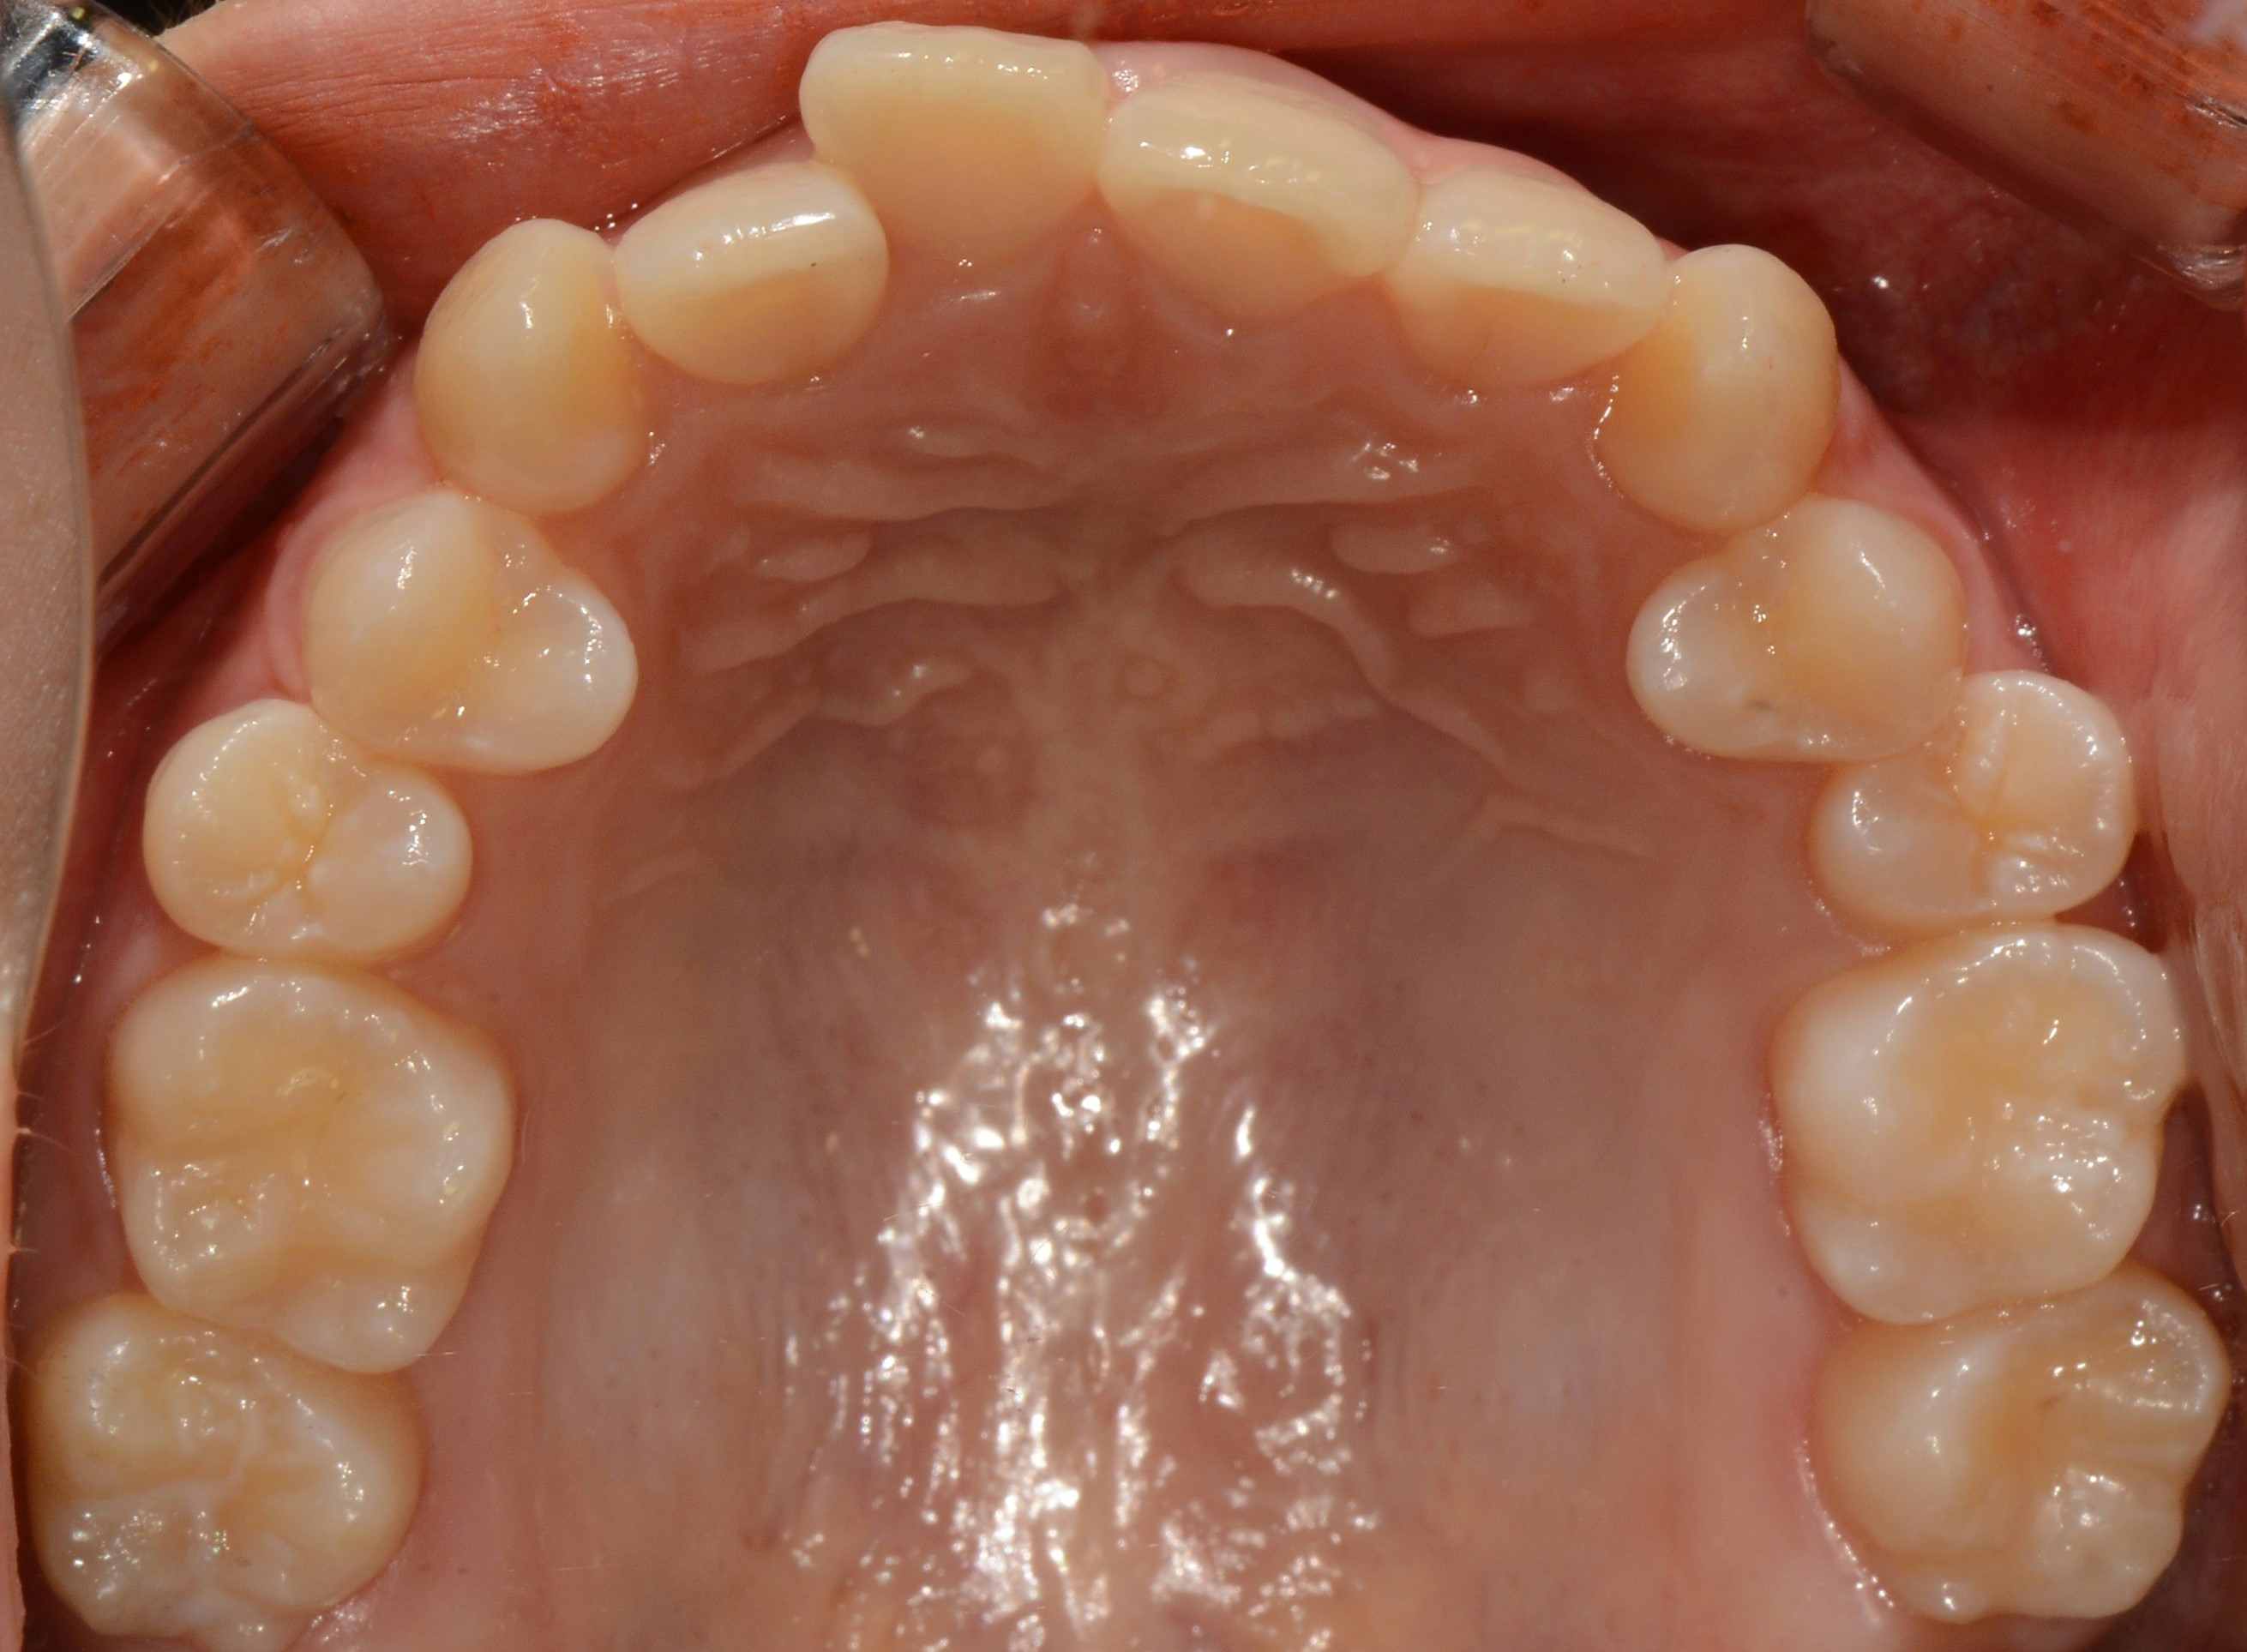

치료 후 사진입니다.